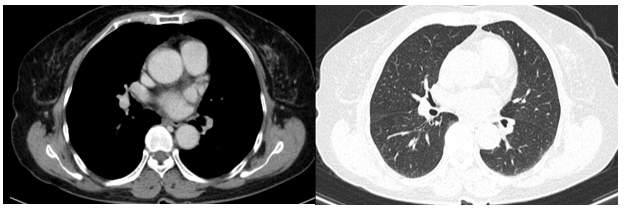

Cắt lớp vi tính ngực: Không phát hiện tổn thương bất thường.

Hình 3: Không phát hiện hình ảnh bất thường trên phim cắt lớp vi tính ngực.